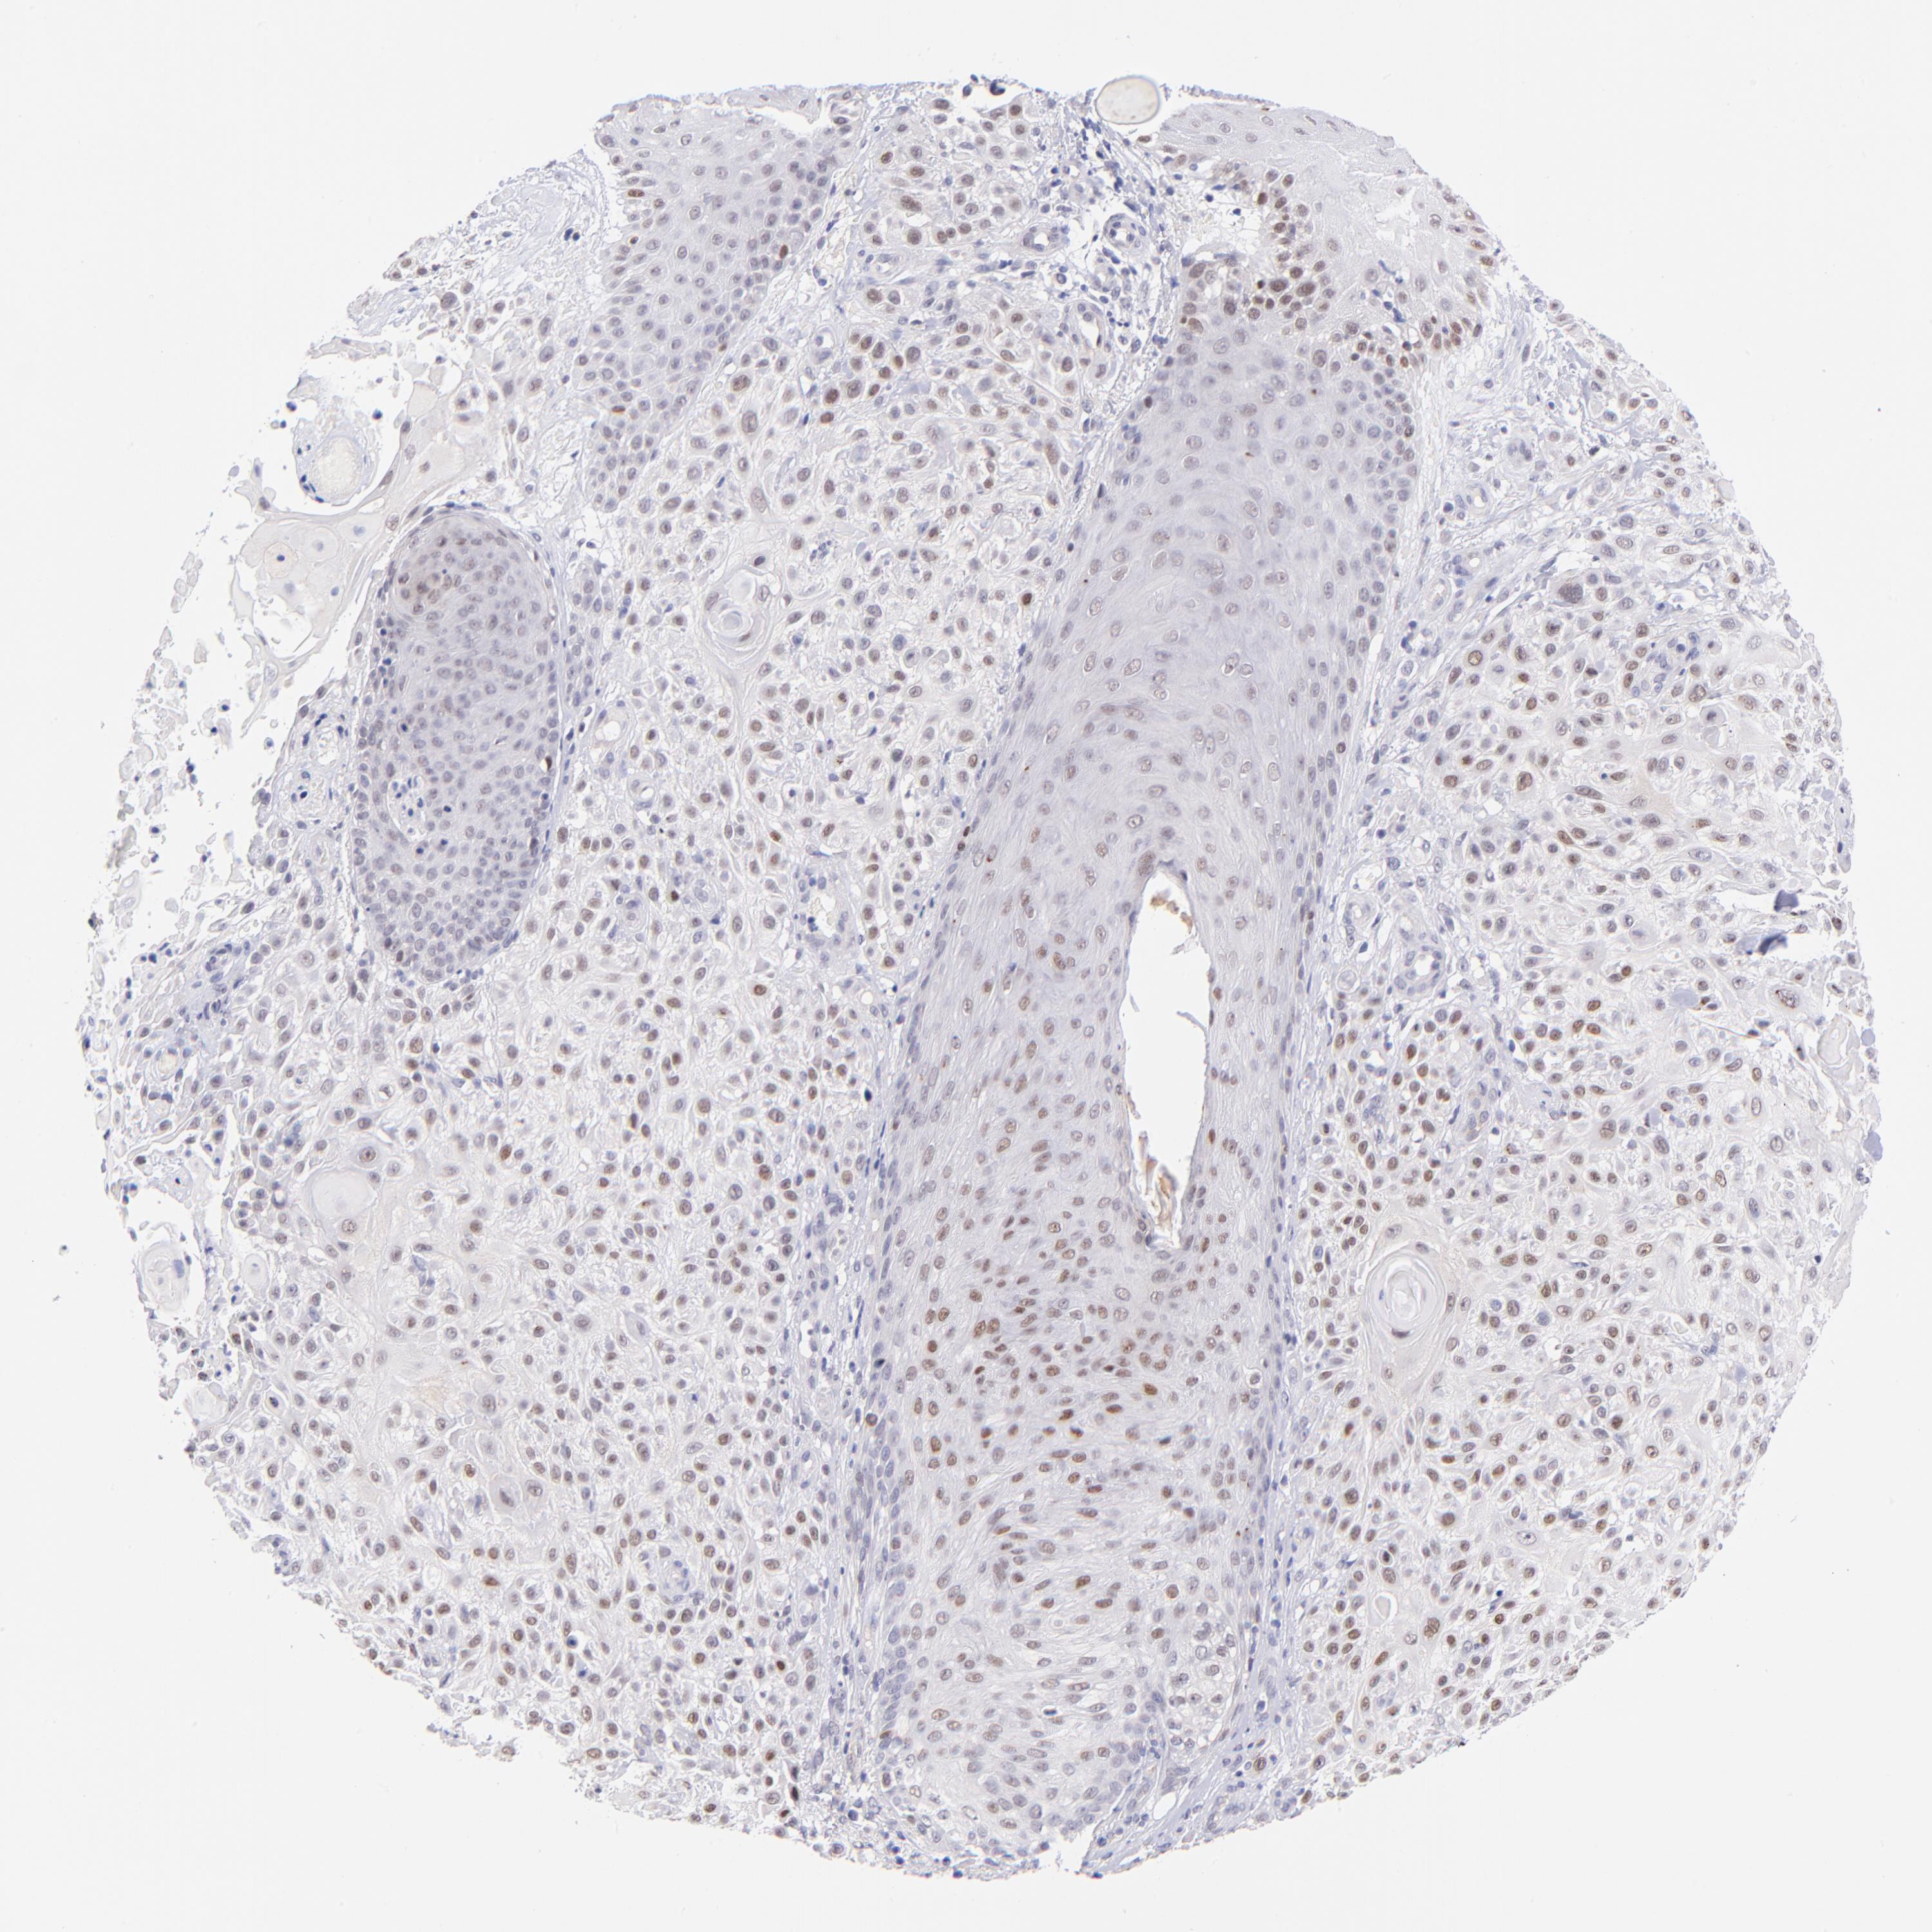

SKIN CANCER - Protein expressioni

A mouse-over function shows sample information and annotation data. Click on an image to view it in a full screen mode. Samples can be filtered based on level of antibody staining by selecting one or several of the following categories: high, medium, low and not detected. The assay and annotation is described here.

Antibody stainingi

Antibody staining in the annotated cell types in the current human tissue is reported as not detected, low, medium, or high, based on conventional immunohistochemistry profiling in selected tissues. This score is based on the combination of the staining intensity and fraction of stained cells.

Each image is clickable and will lead to virtual microscopy that enables deeper exploration of all samples and also displays staining intensity scores, fraction scores and subcellular localization as well as patient and tissue information for each sample.

Antibody HPA001923

Squamous cell carcinoma, NOS

Basal cell carcinoma